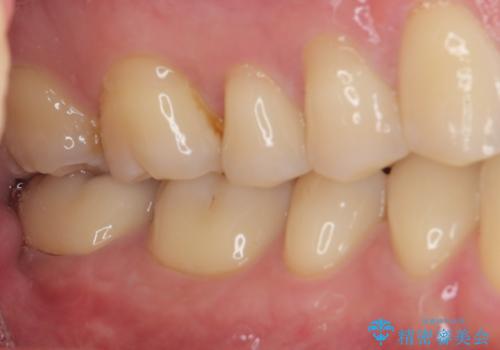

その後は速やかに根管治療を行い、初回の処置以降は痛みや違和感が一気に引いたため、根管治療後にオールセラミッククラウンにて補綴治療を行うこととしました。

治療後は一切痛みや違和感を感じることなく、快適に過ごすことができています。

診断には苦労しましたが、誤った処置を行うことなく、無事に治療を終えることができました。